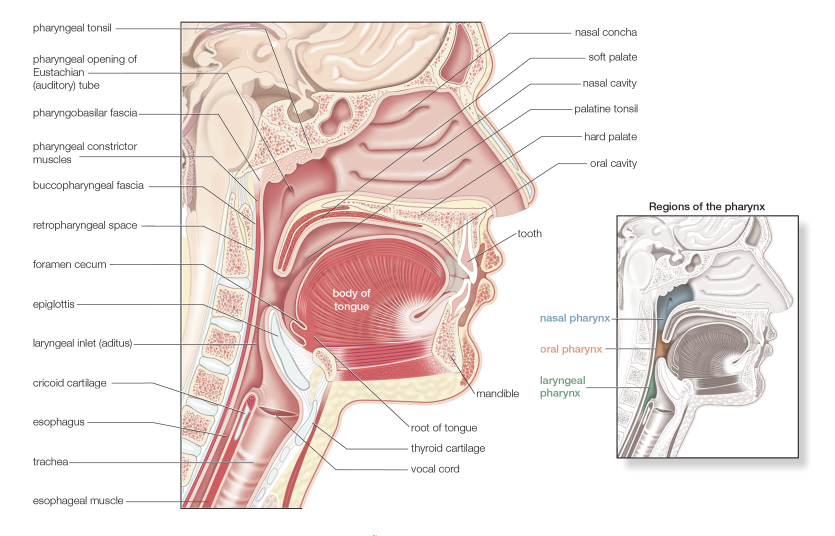

The nasopharynx is posterior to the nasal cavity, inferior to the sphenoid bone, and superior to the soft palate. During swallowing, the soft palate elevates and the pharyngeal wall contracts anteriorly to form a seal, preventing food from refluxing into the nasopharynx and nose. When we laugh, this sealing action can fail, and fluids that are being swallowed while we laugh can end up in the nasal cavity.

The nasopharynx is continuous with the nasal cavity through the arched openings called choanae. The auditory tubes, also known as the pharyngotympanic or eustachian tubes, connect the middle ear to the pharynx and open into the lateral walls of the nasopharynx. The auditory tubes allow middle ear pressure to equalize with atmospheric pressure.

The mucosa that lines the superior part of the posterior wall contains a ring of lymphatic tissue called the pharyngeal tonsil (adenoids), which traps and destroys pathogens that enter the nasopharynx in air (Figure 27-1B).

Much of the mucosa of the nasopharynx posterior to the auditory tubes is supplied by the pharyngeal branch of cranial nerve (CN) V-2 (maxillary nerve), which traverses the palatovaginal canal with the pharyngeal branch of the maxillary artery.

The oropharynx is the region of the pharynx located between the soft palate and the epiglottis and communicates with the oral cavity. The palatoglossal arches mark the boundary between the oral cavity anteriorly and the oropharynx posteriorly. The posterior third of the tongue forms a partial anterior wall of the oropharynx. The mucosa of the oropharynx and the posterior third of the tongue are innervated by the glossopharyngeal nerve (CN IX).

The laryngopharynx extends between the epiglottis and the cricoid cartilage, with the larynx forming the anterior wall. The laryngopharynx serves as a common passageway for food and air. The laryngopharynx communicates posteriorly with the esophagus, where food and fluids to the stomach pass (Figure 27-1B and C). In addition, the laryngopharynx communicates anteriorly with the larynx, where air is conducted in and out of the lungs during breathing. During swallowing, food has the “right of way” and air passage stops temporarily. Innervation of the mucosa of the laryngopharynx is provided by the vagus nerve (CN X).